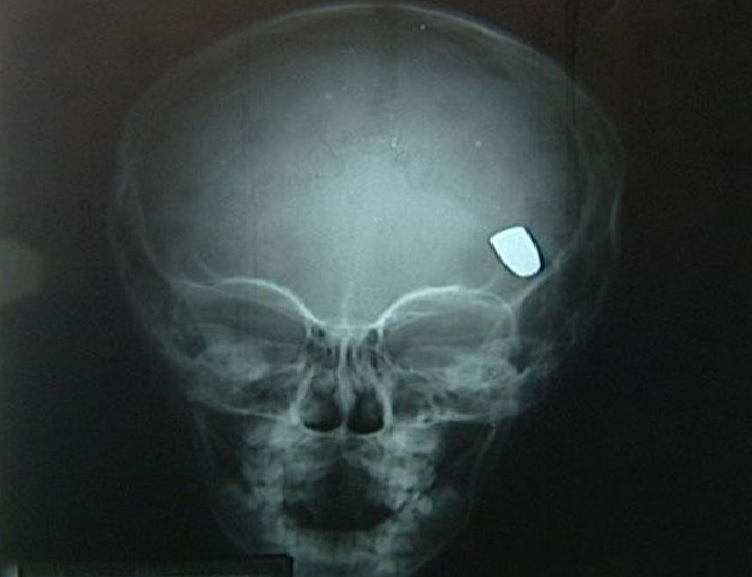

De acordo com informações preliminares, ele teria efetuado um único disparo utilizando um revólver, atingindo a própria cabeça em uma suposta tentativa de tirar a própria vida.

Imagem Ilustrativa